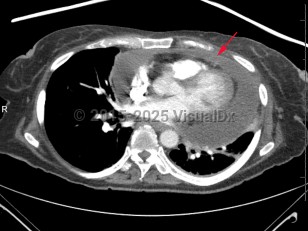

Cardiac tamponadeCardiac tamponade